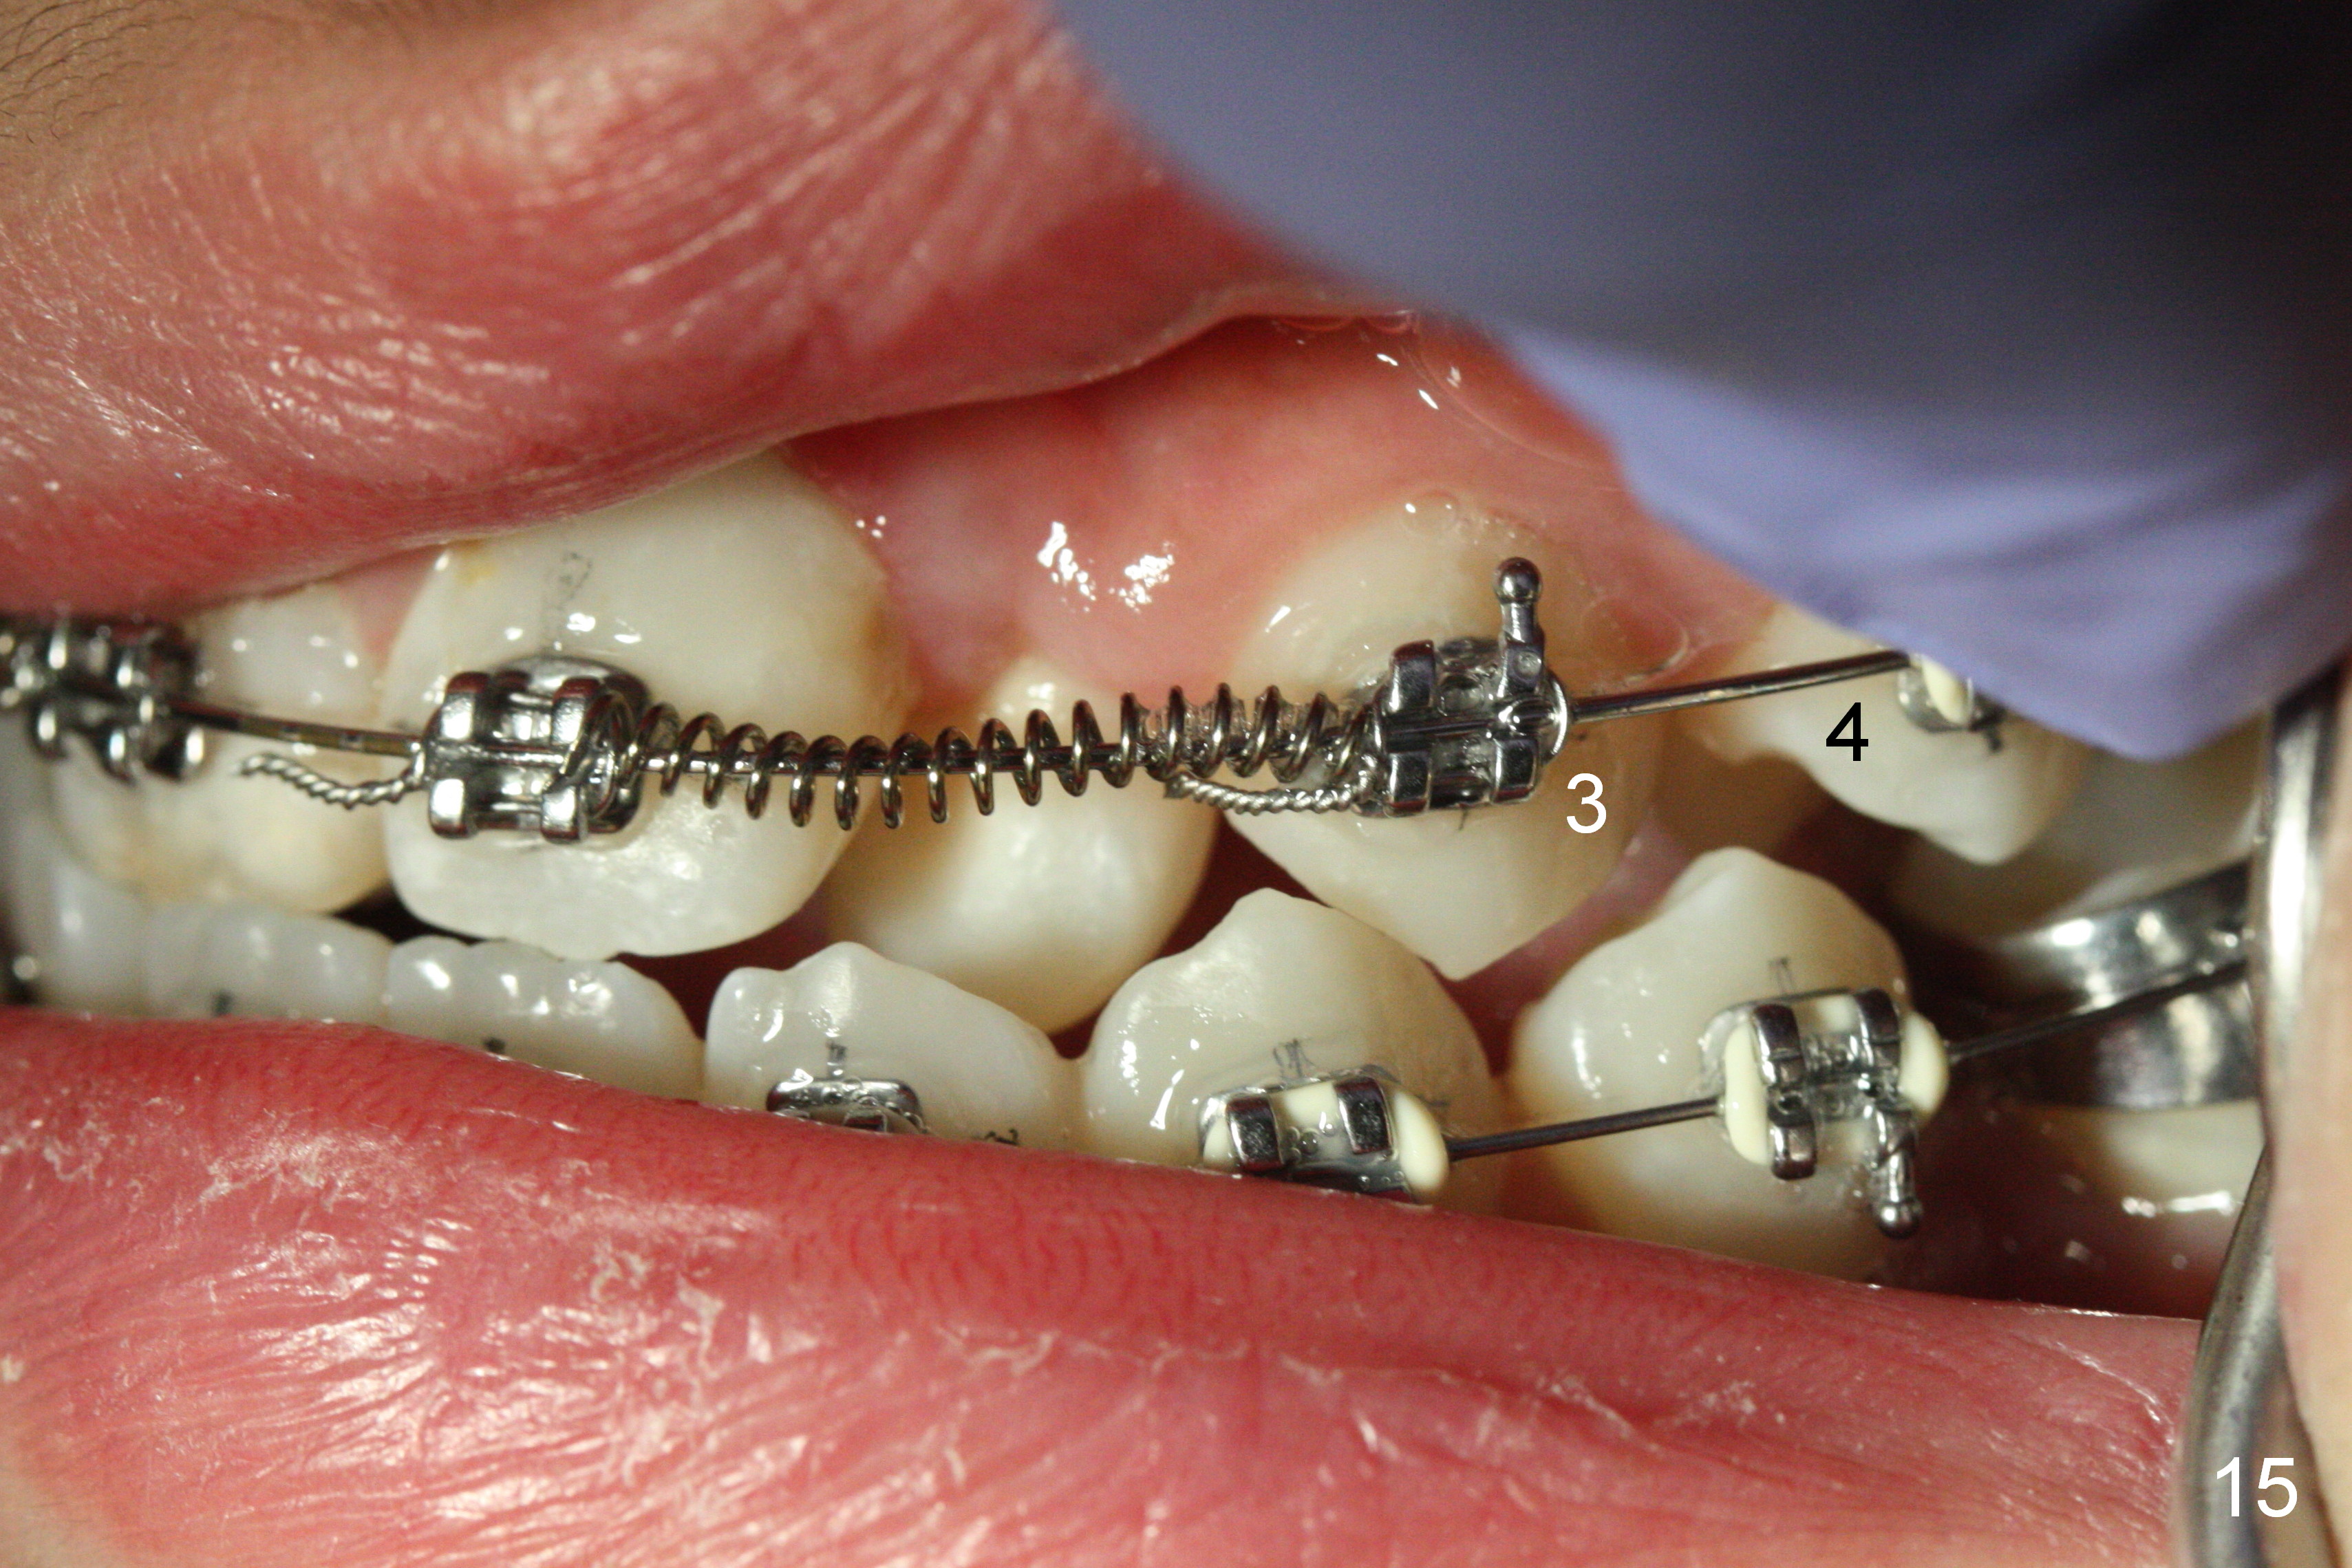

Another 1 month, the right canines (Fig.14: 3, as compared to the left side (Fig.15)) occlude each other, while LR2 has full engagement into .016 niti wire (compare to Fig.12,13). Open coil springs are placed with upper .018' ss arch wire. It must be easier to gain space for UR 2 (Fig.16) than UL2 (Fig.17), because of the presence of space on the right side (4 in Fig.16). There appears no space between UL 4 and 6.